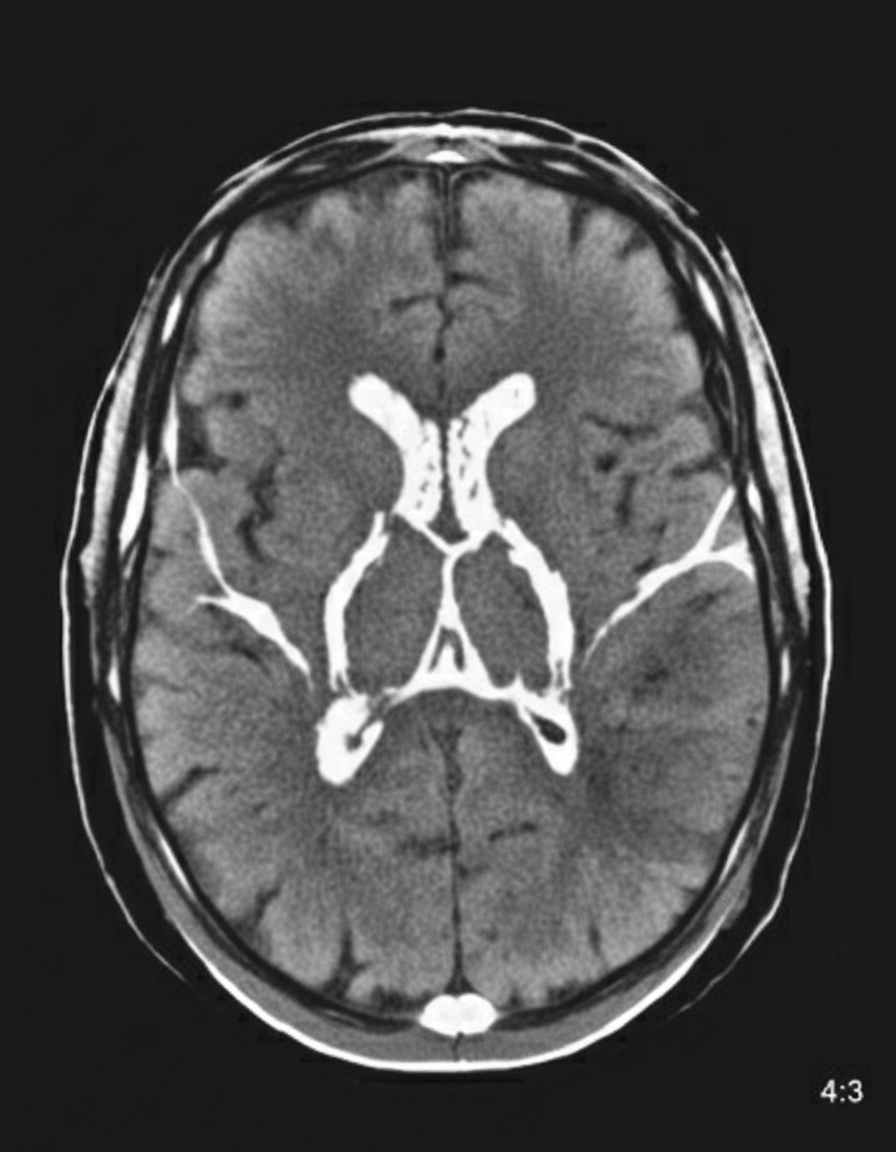

A 48-year-old woman is brought to the emergency department because of a 1-hour history of sudden-onset headache associated with nausea and vomiting. The patient reports she was sitting at her desk when the headache began. The headache is global and radiates to her neck. She has hypertension. She has smoked one pack of cigarettes daily for the last 10 years. She drinks alcohol occasionally. Her father had a stroke at the age 58 years. Current medications include hydrochlorothiazide. She is in severe distress. She is alert and oriented to person, place, and time. Her temperature is 38.2°C (100.8°F), pulse is 89/min, respirations are 19/min, and blood pressure is 150/90 mm Hg. Cardiopulmonary examination shows no abnormalities. Cranial nerves II–XII are intact. She has no focal motor or sensory deficits. She flexes her hips and knees when her neck is flexed while lying in a supine position. A CT scan of the head is shown. Which of the following is the most appropriate intervention?